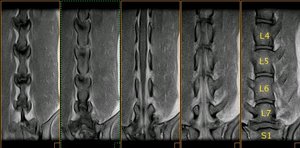

Resonancia magnética (SE T1 sagital) de la columna lumbar |

La médula espinal acaba en L5, donde empieza la cola de caballo |

Resonancia magnética lumbo-sacra de pastor alemán |